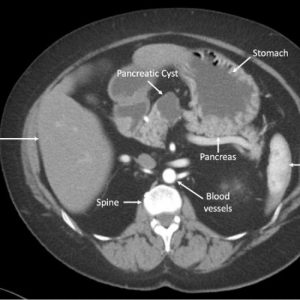

• Test Shown to Improve Accuracy in Identifying Precancerous Pancreatic Cysts